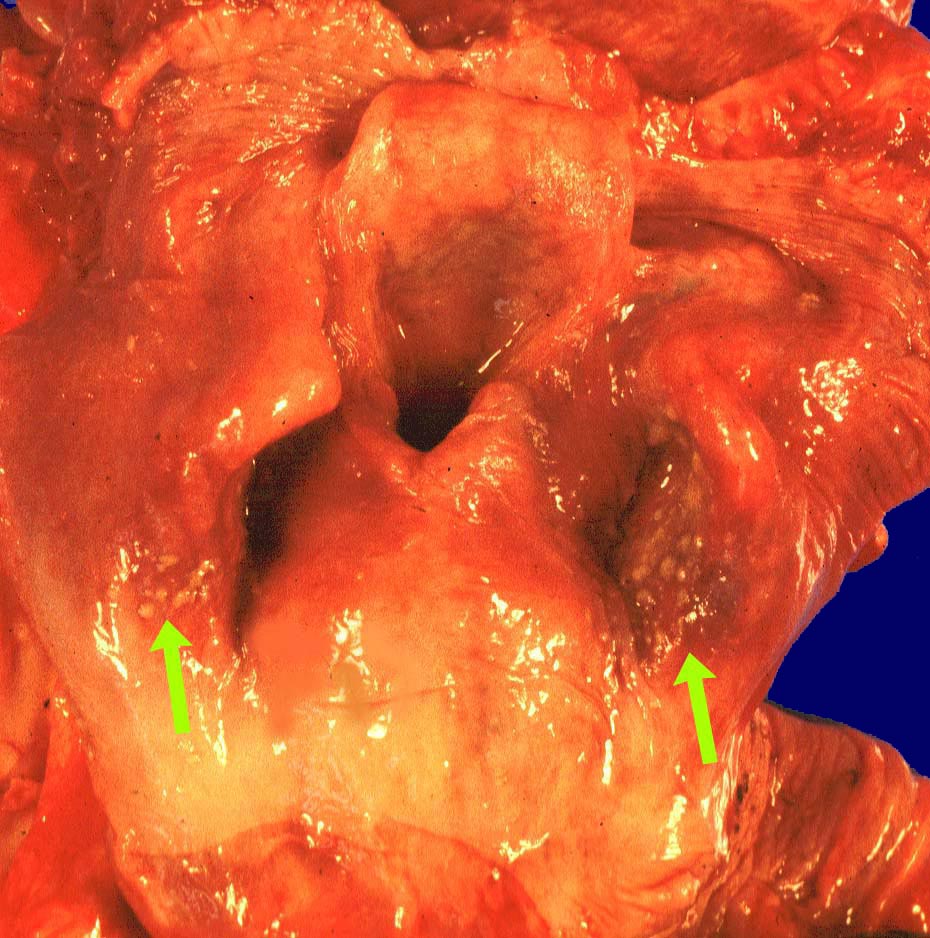

Endoskopisch finden sich abstreifbare weissgelbe krümelige Plaques, welche keine Prädilektionsstelle zeigen. Die Schleimhaut kann erodiert oder ulzeriert sein. In Klumpen von nekrotischen Plattenepithelzellen lassen sich mikroskopisch oft Sporen und Pseudohyphen nachweisen. Die Pseudohyphen wachsen oft senkrecht zur Epitheloberfläche. Besonders gut sichtbar werden die Pilze in der PAS oder Grocott Färbung. Zusätzlich besteht eine aktive Ösophagitis mit Infiltration der oberflächlichen Plattenepithelschicht durch neutrophile Granulozyten. Zahlreiche neutrophile Granulozyten in einem Ulkus weisen auf eine Soorösophagitis. Bei viral bedingten Ulzera (Herpes, CMV) prädominieren Makrophagen.

• Teils ulzerierte, teils erodierte Ösophagusmukosa.

• Die Pseudomembran über der ulzerierten Schleimhaut setzt sich zusammen aus einem dichten Netzwerk PAS positiver Soorpseudohyphen und ovale aussprossende Sporen, nekrotischem Plattenepithel, Fibrin und neutrophilen Granulozyten.

• Die Pseudohyphen infiltrieren das Plattenepithel.

• Im Unterschied zur Aspergillose dünnere Pseudohyphen ohne echte Verzweigungen und zahlreiche Sporen.